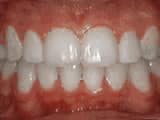

Spacing of teeth

Before

AfterThe patient was bothered by the spaces between his teeth. Braces closed the spaces and gave him an ideal bite in 24 months. Special glued-in retainers help keep the spaces closed.